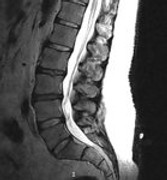

Was in der MRT Aufnahme Juli 2018 auffällig ist, sind die unterschiedlichen Höhen und die Farben der BS.

Je dunkler die BS, desto größer ist der festgestellte Wasserverlust der BS.

Diese Einbuchtungen an den Deckenplatten und hellen Stellen, sind aus meiner Sicht eher ein Hinweis auf Morbus Scheuerman.

Das ist eine Wachstumsstörung durch zu schnelles körperliches Wachstum in Kindheit und Jugend.

Die BWS zeigt auch schon schmale BS Fächer.

Was mir auch aufgefallen ist, dass die Aufnahme einen kl. Versatz von L5 zu S1 zeigt.

Zumindest steht L5 nicht mehr parallel zu S1 und kippt nach dorsal leicht ab

Das deutet auf Instabilität, bzw. Gleitwirbel hin und würde auch erklären, warum Stehen Beschwerden erzeugt.

Das ist mir auch aufgefallen und einem! Radiologen, ansonsten hat nie jemand was dazu gesagt. Ich gehe auch davon aus, dass dies die Schmerzverursache ist.

Okay, das ist ebenfalls ein Aspekt, den noch keiner angesprochen hat.

Ich habe nochmal die MRTs bemüht. Ja, jetzt sehe ich das auch, auch wenn es imho nicht viel ist.